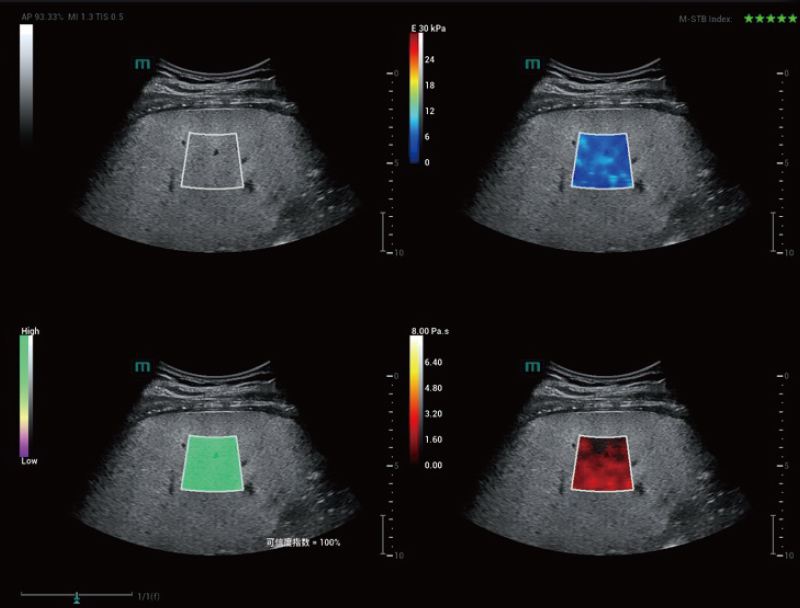

STVi consente la valutazione quantitativa della viscosit├Ā dei tessuti e fornisce immagini multiparametriche in tempo reale, offrendo un approccio pi├╣ completo alla diagnosi per immagini e all'analisi quantitativa di malattie epatiche croniche, lesioni mammarie e altre condizioni.

Coefficienti quantitativi doppi

Valutazione della malattia epatica cronica

Strumenti di quantificazione multipli

Valutazione del tumore al seno